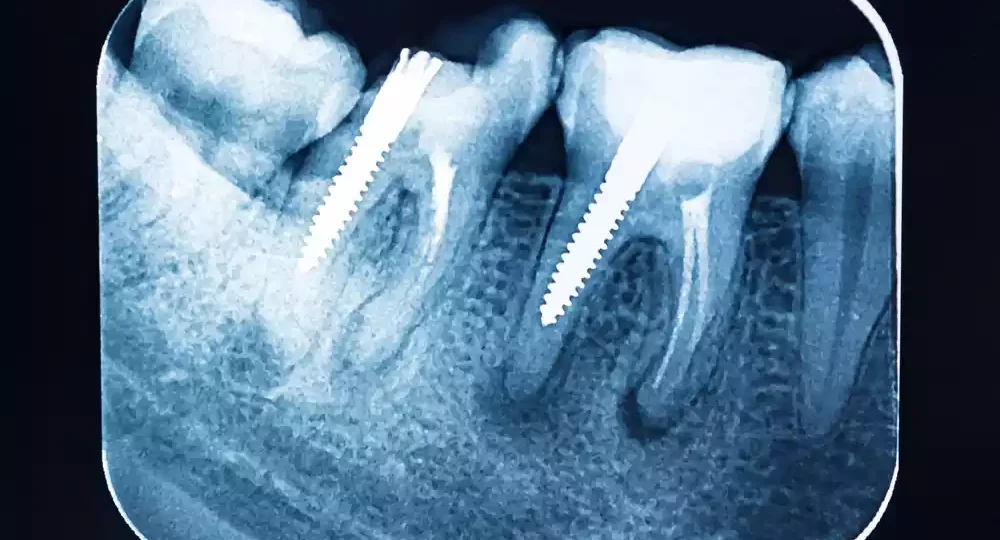

A successful dental implant should feel stable and secure in the jawbone. If you notice any movement or loosening of the implant, it could be a sign of implant failure. Mobility in the implant indicates that it has not properly integrated with the bone or that bone loss is occurring around the implant.

Before diving into the failed implant symptoms, it’s essential to know what dental implant failure entails. Dental implant failure can occur when the implant does not properly integrate with the jawbone or when it becomes unstable over time. This can result from several factors, including poor bone quality, infection, inadequate oral hygiene, or excessive stress on the implant.